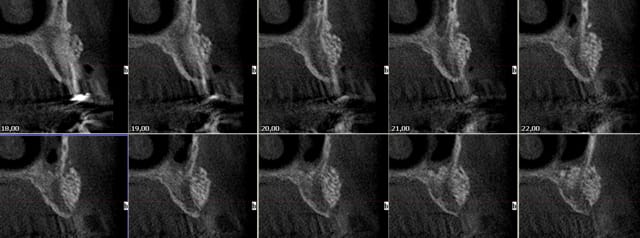

http://www.slide.com/r/mhvTCAqx5T8TRmxaYNA8spDb4u_BIIL6?previous_view=mscd_embedded_url&view=original

j'ai implanté la semaine dernière, la densité, je dirais D4-D3

matériau de ROG biphasé:HA + béta TCP grosse granulométrie.

le matériau était forable, stable et bien solidarisé à l'os d'origine (bien que le cliché radio puisse nous en faire douter)